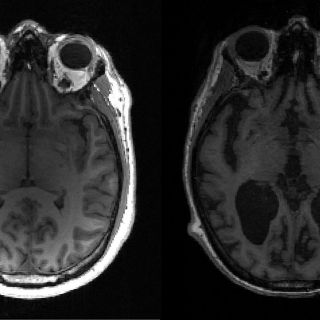

En la enfermedad de Alzheimer, tau y otra proteína llamada beta amiloide se acumulan en nudos y placas -conocidos ambos como agregados- que matan las células cerebrales y encogen el cerebro.

Esto, a su vez, se traduce en pérdida de memoria, cambios de personalidad e incapacidad para realizar funciones cotidianas. Se estima que 44 millones de personas padecen la enfermedad en todo el mundo.